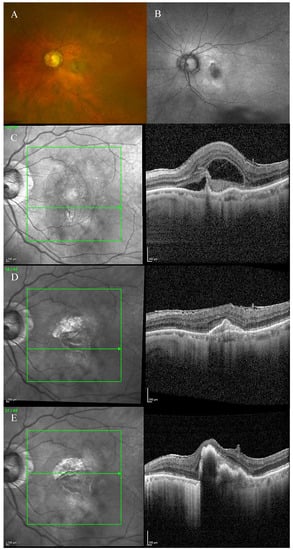

Fundus examination showed macular drusen in the right eye and a macular yellowish elevated lesion with retinal haemorrhage in the left eye (Figure 1A). Autofluorescence imaging (FAF) showed a hypoautofluorescent macular lesion in the left eye (Figure 1B). An OCT scan was performed, showing a dry macula with drusen in the right eye and a type 2 macular neovascularization (MNV) with subretinal fluid and splitting at the ellipsoid zone (EZ) creating a hypo-reflective cavity in the left eye; a hyper-reflective band, continuous with the EZ layer, was observed on the floor of the BALAD (Figure 1C).

Figure 1.

Case 1. Multimodal imaging features of bacillary layer detachment (BALAD) in a patient with left eye neovascular age-related macular degeneration. (A) Optos Ultra-widefield colour shows a macular yellowish elevated lesion with subretinal haemorrhage. (B) Optos Ultra-widefield autofluorescence imaging shows a hypoautofluorescent macular lesion. (C). Heidelberg Spectralis optical coherence tomography shows a type 2 macular neovascularization with splitting at the ellipsoid zone creating an hypo-reflective cavity and a hyper-reflective band on the floor of the BALAD. (D) Optical coherence tomography shows a complete resolution of BALAD after four anti-vascular endothelial growth factor intravitreal injections. (E) Heidelberg Spectralis optical coherence tomography shows a retinal pigment epithelial tear.

The optical coherence tomography angiography (OCTA) scan confirmed the presence of MNV in the left eye (Figure 2). Based on clinical findings and multimodal imaging, the patient was diagnosed with left nAMD. Anti-vascular endothelial growth factor (VEGF) intravitreal injections were commenced, according to a treat and extend (T&E) regimen. To date, the patient received four intravitreal injections. Since the first injection, the OCT scan showed a complete resolution of the BALAD (Figure 1D). However, a retinal pigment epithelium (RPE) tear was noted (Figure 1E). The BCVA did not improve (1.5 logMAR on the last examination).